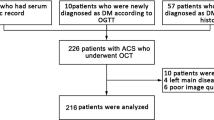

This study is a subanalysis of the EROSION study [11]. For studying the association between glucose-related variables and plaque model of STEMI patients, a total of 1005 patients hospitalized within 24 h of symptom onset in the intensive cardiology care unit of the second affiliate hospital of Harbin Medical University who underwent coronary angiography and optical coherence tomography for STEMI between August 2014 and March 2017 were identified by a search strategy. Excluded those with bad images or categorized as neither PR nor PE, totally 872 patients with PR (n = 656) and PE (n = 216) were identified and divided into two groups according to optical coherence tomography (OCT) imaging. The definition of STEMI and identification of the culprit lesion were described previously [8] and identification of PR and PE was based on established OCT diagnostic criteria [11]. OCT-rupture was defined and categorized according to the imaging of fibrous cap disruption and the presence of thrombus, OCT-erosion was defined and categorized according to the absence of fibrous cap disruption and the presence of thrombus. The optimal medical therapy for STEMI was administered in every patient during hospitalization, according to the current guidelines.

Quantitative coronary angiography (QCA) was performed using the Cardiovascular Angiography Analysis System (CAAS, 5.10, Pie Medical Imaging B.V., Maastricht, the Netherlands). Culprit vessels and lesion sites were identified, and the length of the culprit lesions, reference vessel diameter, minimal lesion diameter, and degree of diameter stenosis were measured. OCT data were recorded using the C7-XR OCT intravascular imaging system (OCT C7 Dragonfly, St. Jude Medical, St. Paul, MN, USA). Quantitative and qualitative analyses of underlying plaques were performed by two independent operators as described in a previous study [10]. Any discordance was resolved by consensus with a third reviewer. Using established diagnostic criteria [12], the plaque and thrombus type were identified based on established OCT diagnostic criteria, along with identification of microchannels, cholesterol crystals, macrophages, and thin-cap fibroatheroma (TCFA). The lesion length, minimal lumen area, minimal thickness of the fibrotic cap, length of the residual thrombus, length of the lipid core, maximal arc of the lipid core, and average arc of the lipid core were measured as described previously [13] (Fig. 1)